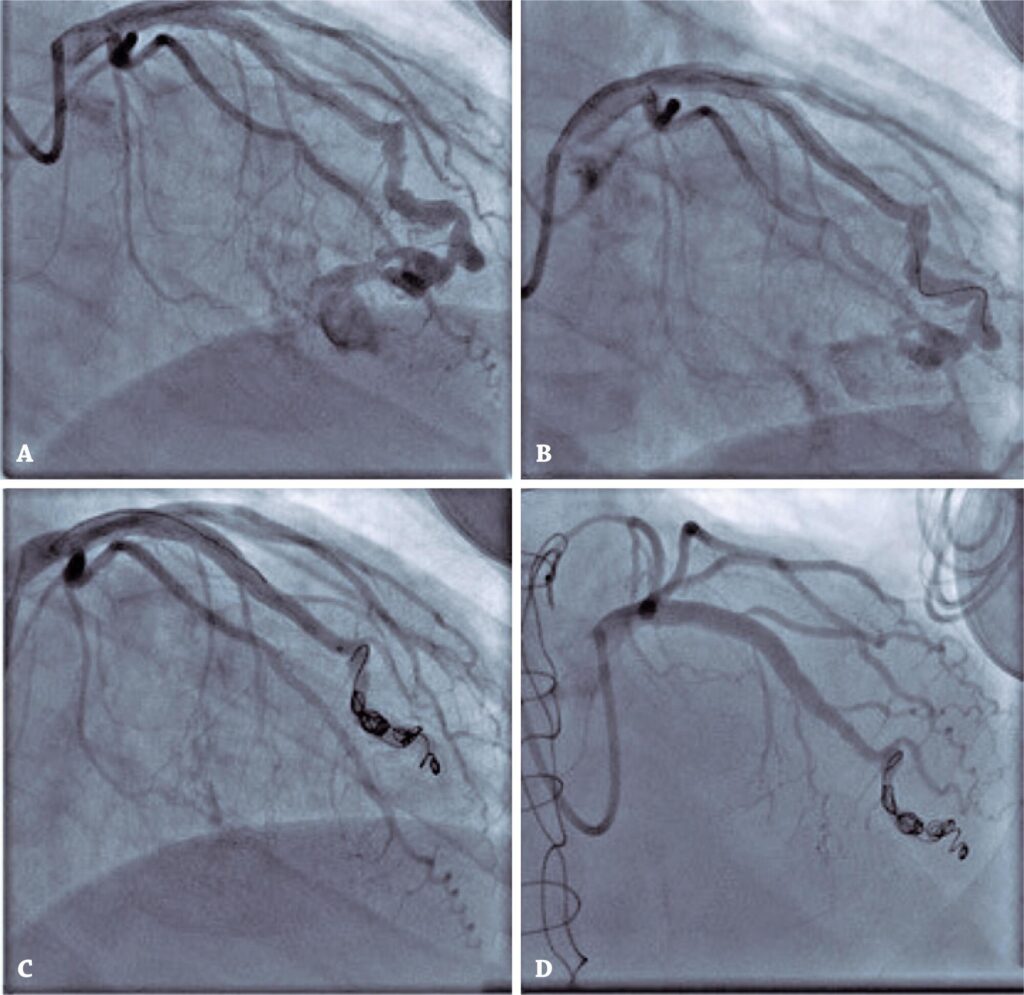

Após o resultado de isquemia na cintilografia, foi realizada cineangiocoronariografia, que exibiu fístula entre a artéria descendente anterior e o ventrículo direito, com oclusão coronária após sítio de fístula (). Esta é uma complicação rara da biópsia endomiocárdica.

Figura 1

(A) Fístula entre a artéria descendente anterior e ventrículo direito com oclusão coronariana subsequente. (B e C) Implante dos coils. (D) Angiografia final.